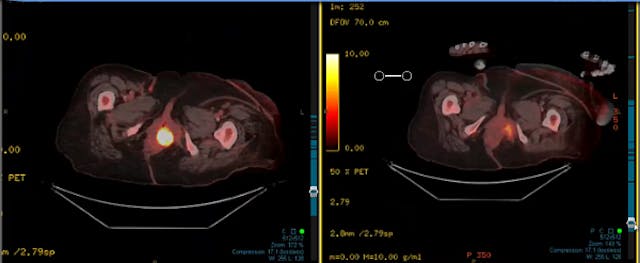

04/18/2024 - Dr. Christine Fisher - Radiation Oncology - GYN

Chartrounds US - GYN